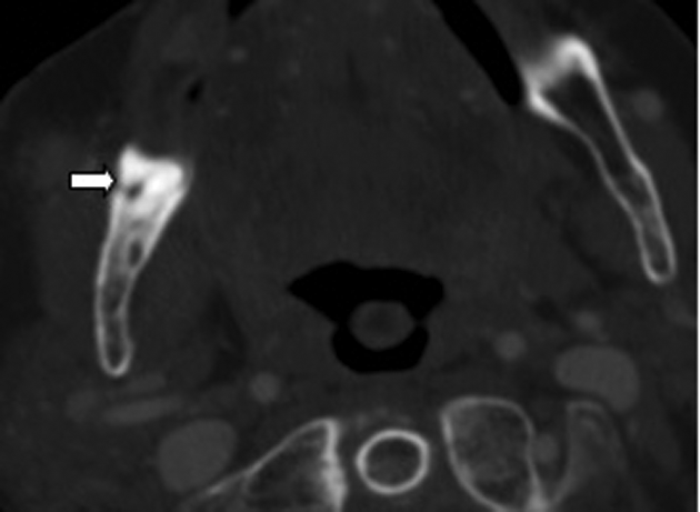

Clinical examination excluded a dental cause, as the patient was edentulous, however an ultrasound demonstrated an abscess over the right masseter muscle. Figure 3 shows an abscess collection in the right buccal space. Figure 4 demonstrates the cause of the abscess (and otalgia) - a tooth root buried underneath the gingiva, with associated buccal bone perforation.

Figure 4: Bone window axial CT demonstrating a retained root (white arrow).

Dental disease, most commonly caries and impacted lower wisdom teeth, are frequent causes of referred otalgia. The imaging modality of choice in the assessment of teeth is radiography.

A commonly used radiograph is the orthopantotomogram (OPT). An OPT is a horseshoe shaped tomographic slice of both jaws, which can be useful in the assessment of caries, periodontal and periapical infections (Figure 5). It is a technique which is prone to positional errors and artefacts which can affect reliability of interpretation. Cone beam CT is being increasingly used in the dental profession but its use specifically for caries assessment is not recommended [2].